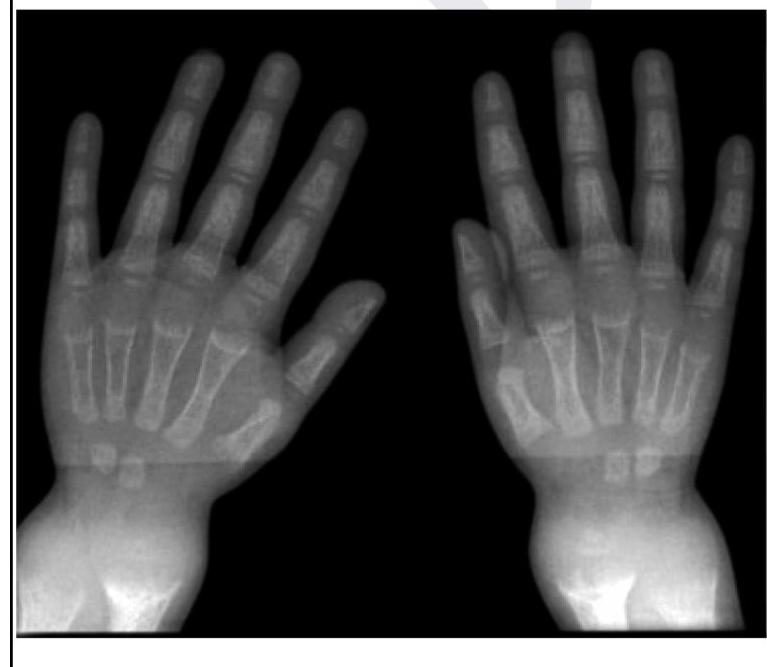

A child presents with poor growth and swelling at joints. A radiograph of his wrist is given below. Lab investigations reveal serum ALP levels of >1500. What is the possible diagnosis?

Explanation: ***Rickets*** - The combination of **poor growth**, **joint swelling**, and **elevated alkaline phosphatase (ALP)** in a child strongly indicates rickets, a condition of defective bone mineralization in growing bones. - The radiograph of the wrist would likely show typical findings like **widened growth plates**, **fraying** and **cupping of metaphyses**, and **decreased bone density**, which are characteristic of rickets. *Osteoporosis* - This condition is characterized by **reduced bone mass** and **fragile bones**, typically seen in older adults or due to secondary causes, and is not primarily linked to joint swelling in children. - While ALP levels can be normal or slightly elevated in osteoporosis, a level of >1500 is highly suggestive of active bone formation or breakdown, not typically seen in osteoporosis. *Osteomalacia* - This is defective bone mineralization in adults after growth plates have fused, leading to **bone softening** and **pain**, typically not presenting with joint swelling as a primary symptom. - While it also involves high ALP and bone demineralization, the clinical context of a *child* with growth issues points more specifically to rickets. *Osteogenesis imperfecta* - This is a group of **genetic disorders** characterized by **brittle bones** that fracture easily, often accompanied by **blue sclerae** and **hearing loss**, which are not mentioned in the presentation. - While bone fragility is present, it does not typically cause the described joint swelling or the significantly elevated ALP levels seen in this case.